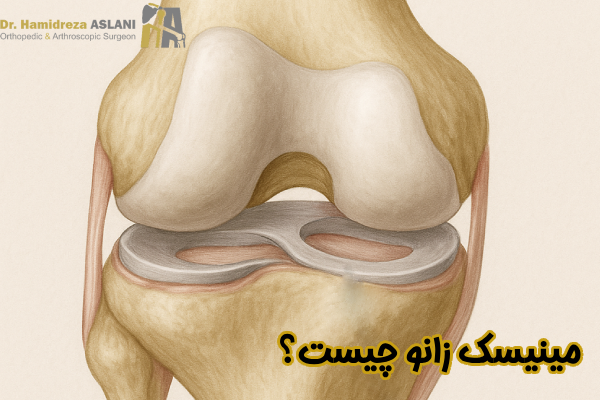

مینیسک زانو چیست؟

مینیسک زانو یک ساختار فیبروغضروفی هلالی شکل است که در فضای بین استخوان ران و استخوان ساق پا قرار می گیرد و بخشی حیاتی از سیستم بیومکانیکی مفصل زانو به شمار می رود. این بافت به گونه ای طراحی شده که بتواند نیروهای وارد شده به زانو را جذب، توزیع و هدایت کند تا فشار مستقیم به غضروف و استخوان منتقل نشود. مینیسک ها علاوه بر نقش ضربه گیری با افزایش سطح تماس بین استخوان ها باعث روان تر شدن حرکت مفصل و کاهش اصطکاک می شوند. ساختار الیافی و نیمه سخت آنها به گونه ای است که در عین انعطاف پذیری، توان تحمل فشارهای بالا را دارد و همین ویژگی مینیسک را به یکی از مهمترین عناصر پایداری و عملکرد طبیعی زانو تبدیل می کند.

مینیسک زانو دو ساختار هلالی شکل از جنس غضروف فیبری است که در فضای بین استخوان ران و استخوان ساق پا قرار دارد. این بافت در هر زانو یک مینیسک داخلی و یک مینیسک خارجی دارد و نقش مهمی در جذب فشار، پایداری مفصل و توزیع یکنواخت وزن ایفا میکند. مینیسک ها به عنوان ضربه گیر طبیعی زانو عمل می کنند و از ساییدگی سطوح مفصلی جلوگیری می کنند. محل قرارگیری دقیق آنها باعث شده است که در حرکت، چرخش و خم و راست شدن زانو اهمیت زیادی داشته باشند.

مینیسک زانو یکی از دقیق ترین بافت های بدن است که برای تحمل فشارهای بالا و ایجاد ثبات در مفصل طراحی شده است. این ساختار فیبروکارتیلاژی با ظاهری ساده اما عملکردی پیچیده، نقش حیاتی در هماهنگی استخوان ها، جذب نیرو و حرکت روان زانو دارد. آشنایی با اجزای آناتومیک مینیسک به ما کمک می کند بهتر درک کنیم چگونه این بافت کوچک چنین مسئولیت بزرگی را بر عهده دارد. ویژگی های کلیدی ساختار مینیسک به شرح زیر است:

این شکل باعث می شود مینیسک به طور دقیق میان استخوان ران و ساق قرار گیرد و مانند یک بالشتک طبیعی، تماس و هماهنگی میان سطوح مفصلی را به بهترین شکل برقرار کند.

سطح فوقانی مقعر و سطح زیرین صاف

سطح مقعر بالایی با شکل گرد استخوان ران هماهنگ می شود، در حالی که سطح صاف زیرین روی صفحه تیبیا قرار می گیرد تا مفصل ثبات و حرکت روان تری داشته باشد.